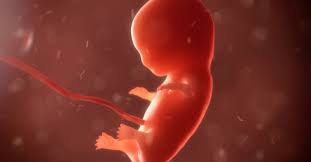

La amenaza de aborto se define como cualquier hemorragia y/o cólico uterino (en la matriz) que se presenta durante los primeros 4 y medio meses del embarazo; cuando no se trata a tiempo y en forma adecuada puede presentarse un ABORTO ESPONTÁNEO.

El aborto espontáneo que se presenta en los 3 primeros meses de embarazo está relacionado con anomalías del embrión, o ausencia de éste (embarazo anembriónico).Cuando se presentan después del 3er mes están más relacionados con problemas maternos como infecciones, malformaciones uterinas, etc.